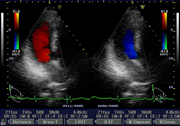

| 心臓の壁の厚さや壁運動異常の有無、心機能の評価を行います。また、ドプラー法により弁の血流状態や逆流の有無もわかります。高血圧症、狭心症、弁膜異常や心不全等の心機能評価に有用です。 |

| 血流や弁の動き(ドプラー) |